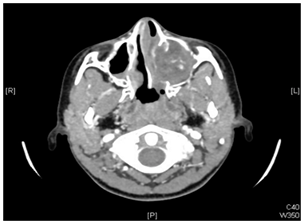

Figure 3 Sagittal CT revealed a large expansile mass occupying the whole left maxillary sinus